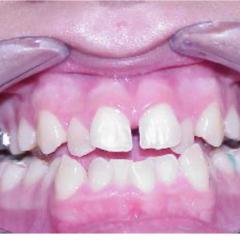

- We are discussing expansion. I am sure, we all have done few. We will revisit protocol.

- There are also other types of expanders besides RPE and we will look intot hem as well.

- Narrow maxilla is indicative of expansion in presense of a crossbite however, expansion is being used as a corrective treatment in Class II and Class III cases as well. We will examine latest literature on the subject.